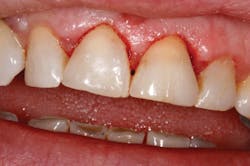

Figure 3: Seven-days post-op

Solea's precision and ability to maintain a clean surgical site allowed this unscheduled procedure to be completed successfully. Additionally, rapid healing was observed (figure 3). With Solea, this was a minimally invasive procedure and crowns were prepared 30 days postoperatively (figure 5). Traditional surgery would require six to eight weeks until proper conditions were established for definitive restorative work. In addition, there would have been more postoperative pain and slower healing with traditional instruments.